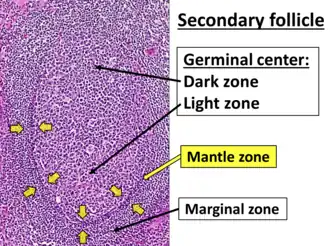

Histology of a normal secondary lymphoid follicle, with yellow arrows pointing at the mantle zone. | |

The mantle zone (or just mantle) of a lymphatic nodule (or lymphatic follicle) is an outer ring of small lymphocytes surrounding a germinal center.[1]

It is also known as the "corona".[2]

It contains transient lymphocytes.[3]

It is the location of the lymphoma in mantle cell lymphoma.